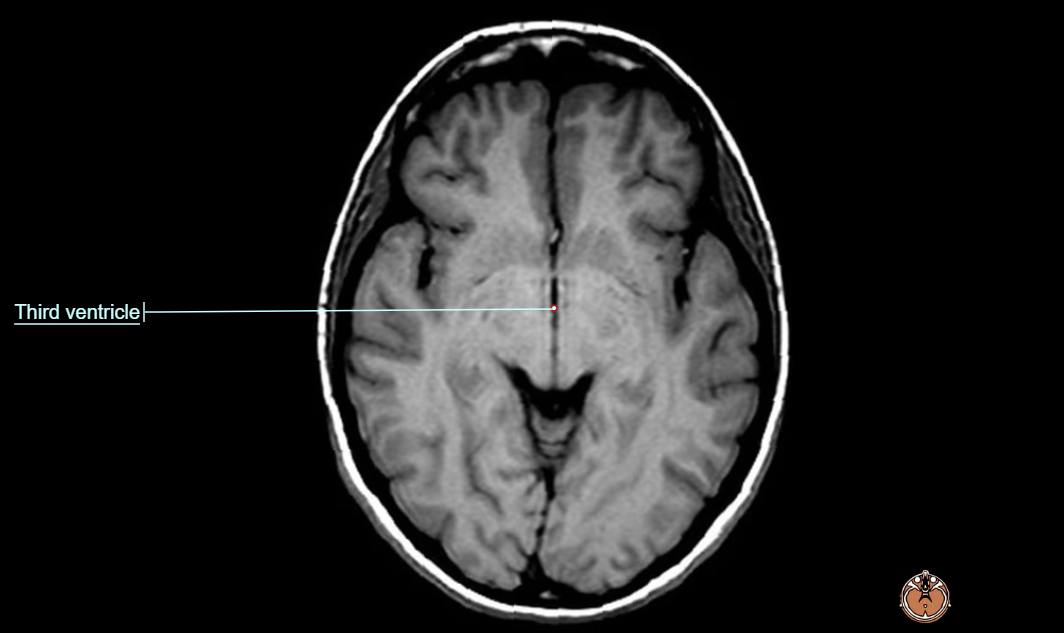

- 뇌 MRI(brain MRI) 영상은 T2 flair 및 brain DWI 영상에서 아래와 같은 영역에서 양측성 signal intensity의 증가 소견을 보이게 된다.

- around the third ventricle

- 흔히 병변이 확인되는 구조물 : the 3rd ventricle, aqueduct, fourth ventricle, dorsomedial thalamus, locus ceruleus, peri-aqueductal gray, ocular motor nuclei, vestibular nuclei, fornices, septal region, hippocampus, cerebral cortex 등에서 보이며, 주로는 대칭적으로 확인된다.